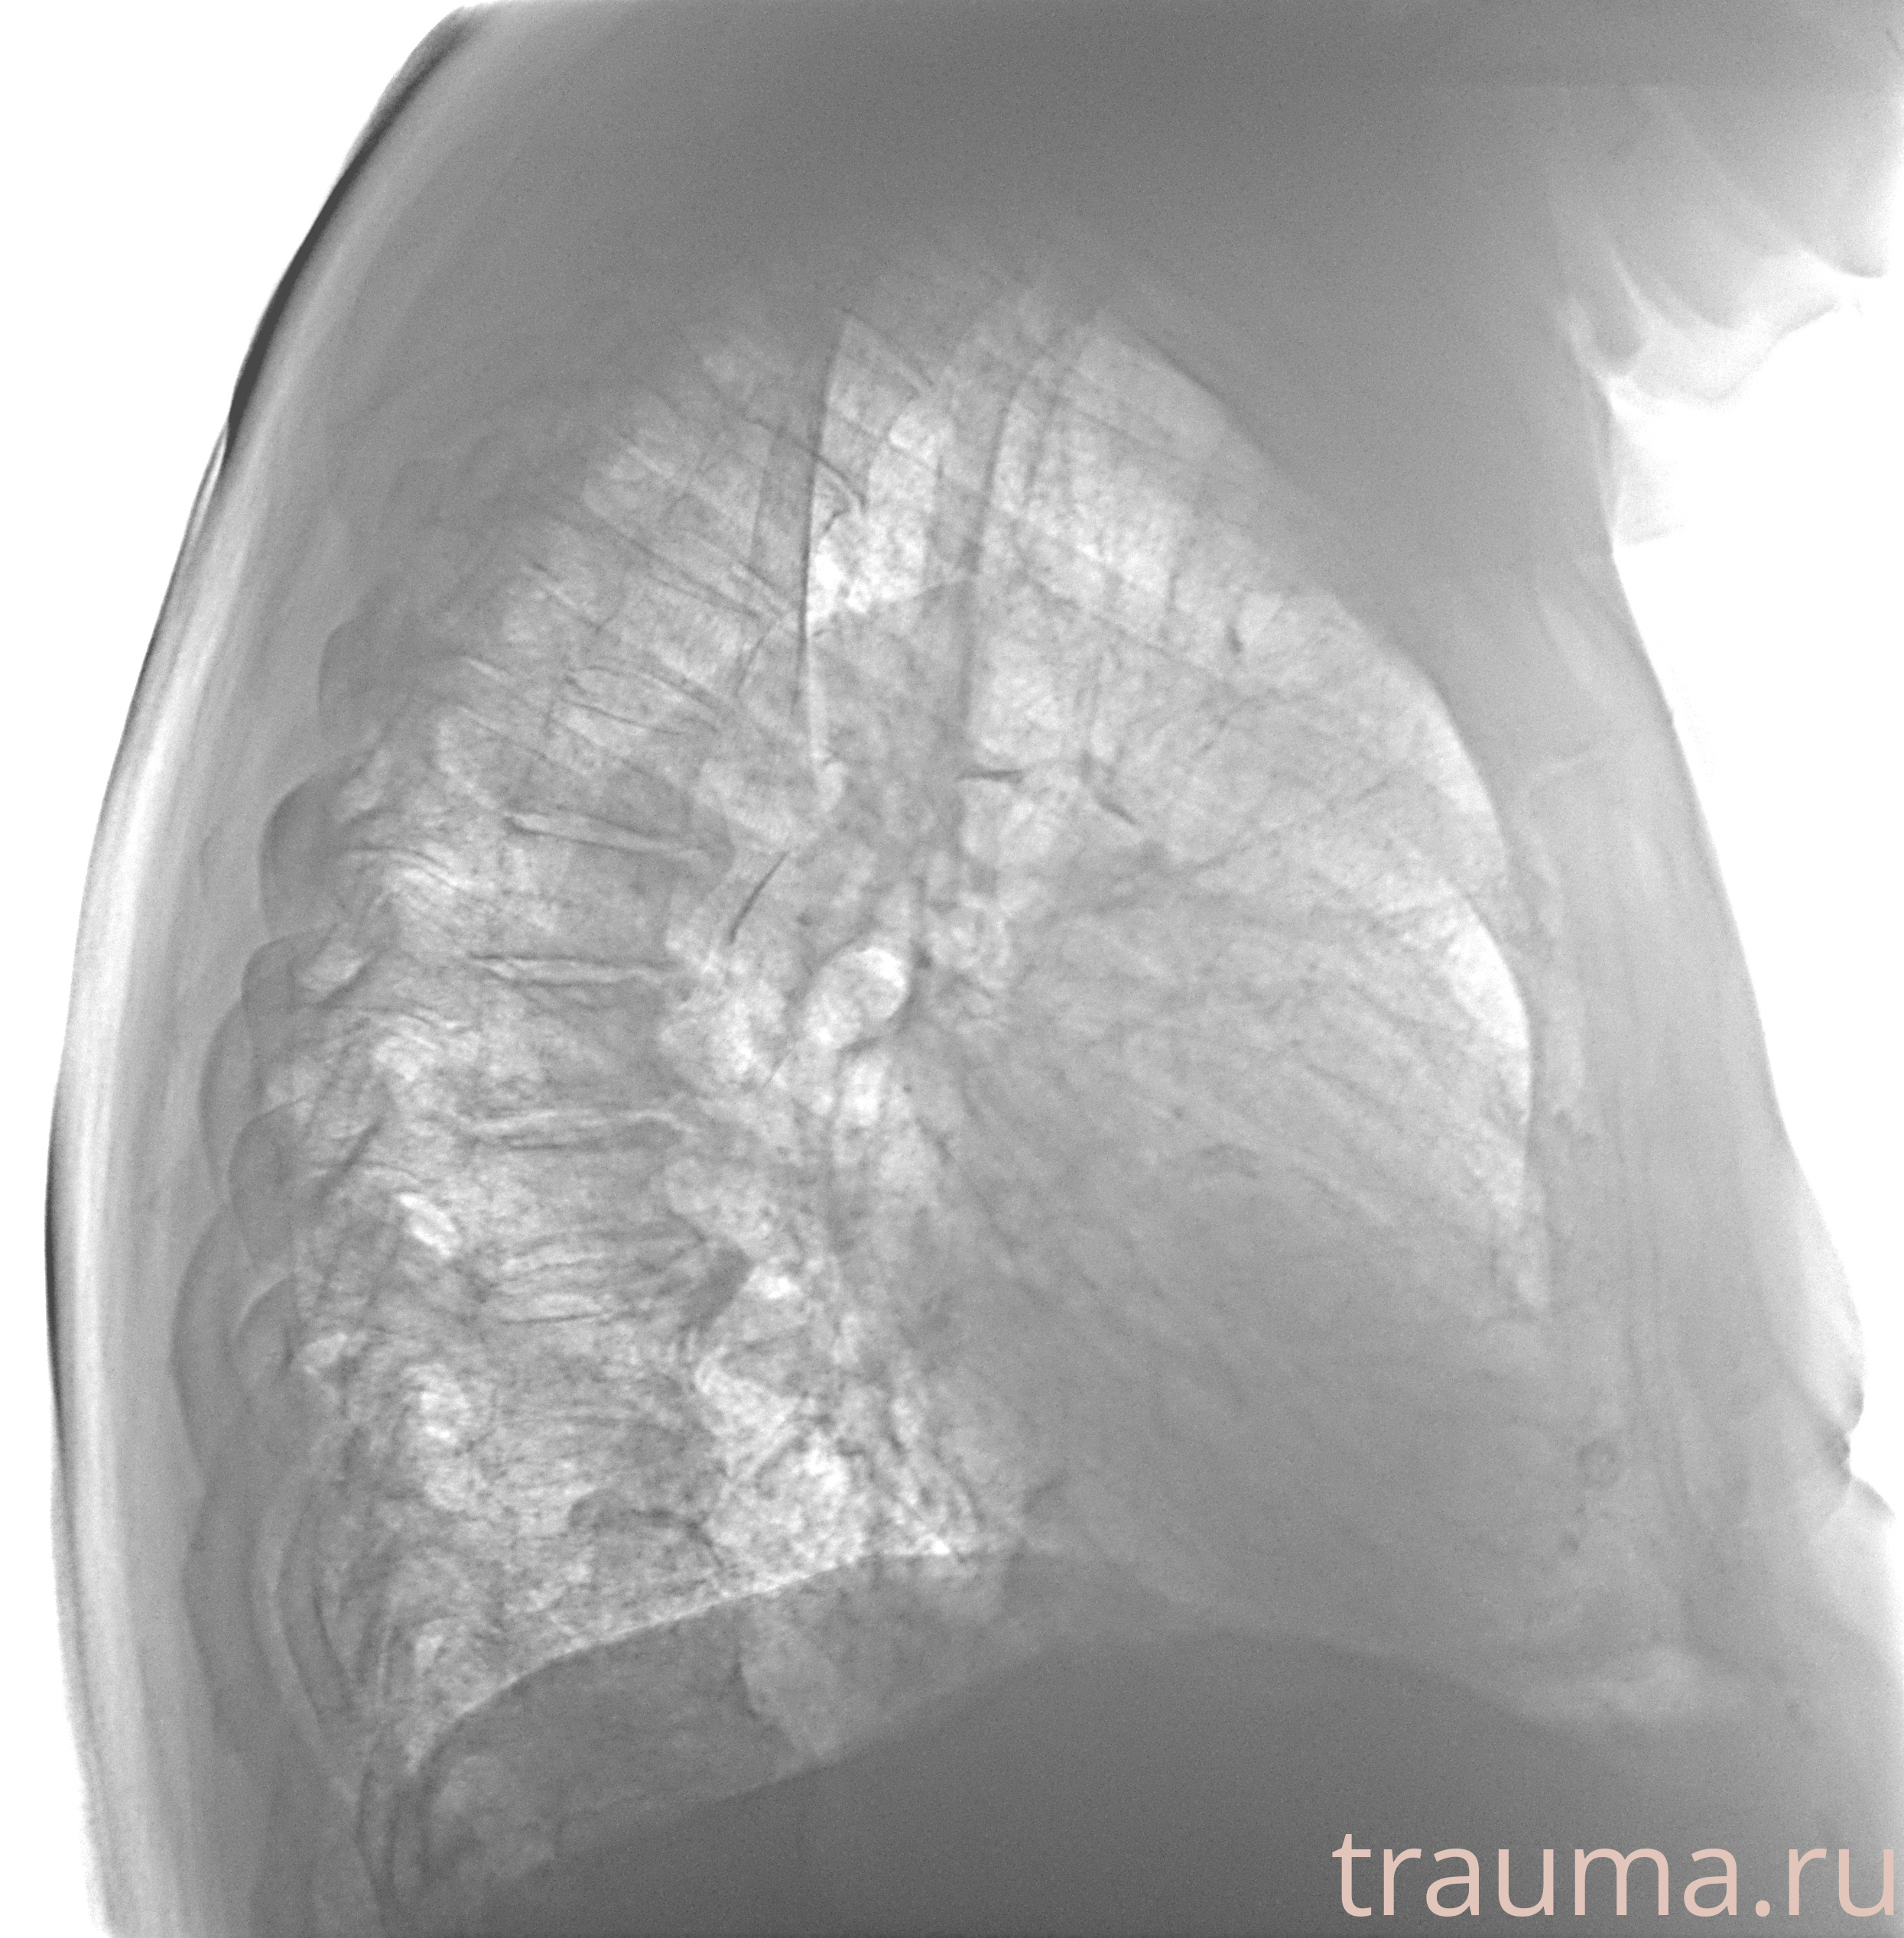

Рентгенограммы

Рентген на дому: по вашему адресу приезжает врач-рентгенолог, травматолог-ортопед с мобильным рентгеновским аппаратом, проводит диагностику травмы или заболевания, делает необходимые рентгенограммы, дает рекомендации по дальнейшему лечению. Получить качественные снимки в домашних условиях возможно благодаря уникальной методике, разработанной МосРентген Центром для института  Склифосовского

Яркость: 1   Контраст: 1   Инвертировать: 0 Увеличение: 1

Перетаскивайте мышь вверх/вниз для контраста, влево/право для яркости. Прокрутка колесом изменяет масштаб. Нажмите Сбросить для возврата к исходному изображению. При увеличении держите мышь в той области, которую хотите рассмотреть.